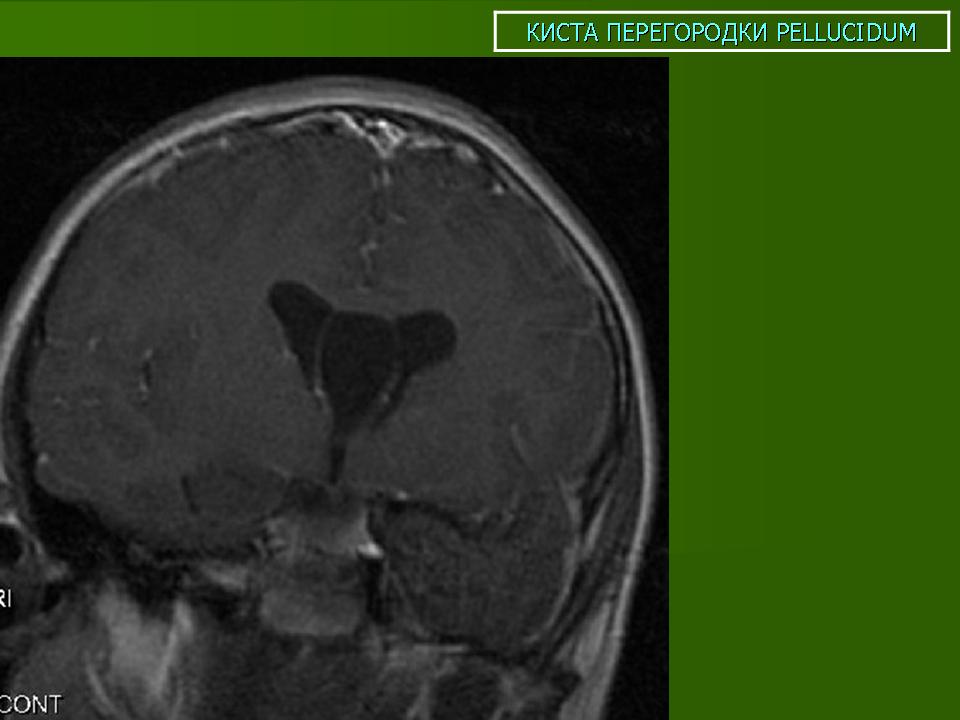

ГМ. Киста прозрачной перегородки. +

Киста прозрачной перегородки.

Прозрачная перегородка представляет собой мозговое вещество, которое состоит из двух очень тонких пластиночек. Разделяет их щелевидная полость, которая располагается между мозолистого тела и передней частью мозга. Собственно, киста прозрачной перегородки мозга - это скопление жидкости между пластинками, о которых мы сейчас упоминали. Киста прозрачной перегородки является одной из разновидностей арахноидальной кисты, которая локализована в строго определенном месте мозга.

Кисту прозрачной перегородки современная медицина не относит к разряду патологических отклонений и считает ее аномалией, не представляющем никакой угрозы для жизни больного вариантом анатомического строения мозга. Конечно-же это относится к случаям врожденной кисты прозрачной перегородки мозга, коротая протекает безсимптомно, жалоб у больного не вызывает и лечения не требует.